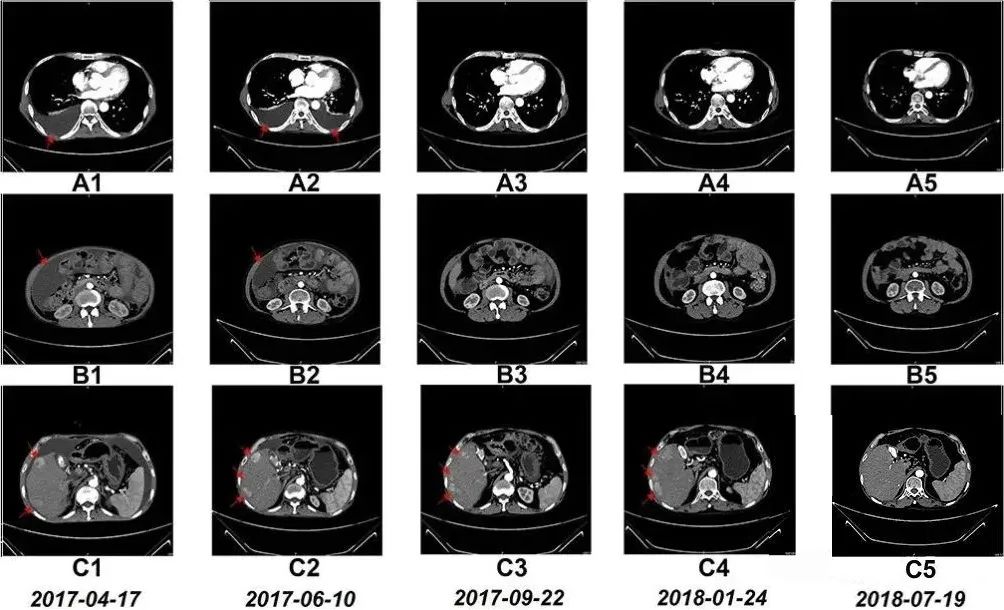

免疫力的提升可以检测,更有望改变抗癌结局。一位晚期肝癌患者每月接受一次NK细胞输注,胸水腹水消退,肿瘤明显缩小,生存期从3个月延长至今。

59岁的程先生连续几日右上腹出现持续性刺痛,加上就诊前有恶心、腹泻、发热等症状,提心吊胆的他在家人陪伴下来到医院检查,不查不知道,一查吓一跳,检查结果显示:胸腔积液(胸水)、腹腔积液(腹水)、肝右叶有多个肿瘤,程先生最后被确诊为弥漫性肝癌晚期(IV期)。

随后的8个月里,患者接受了一系列的手术、化疗和药物治疗。2017年3月,他开始尝试NK细胞输注治疗,值得一提的是,患者在NK细胞治疗期间,除营养支持、心理干预等辅助疗法之外,未接受其他治疗。

令患者本人和医疗团队都格外惊喜的是,7个月后,患者的胸水和腹水明显减少,治疗17个月后,CT扫描显示他肝右叶的多个肿瘤显著缩小。淋巴细胞亚群出现的变化表明免疫功能得到改善。此外,患者的肝功能水平和白细胞、血小板、中性粒细胞和淋巴细胞计数也保持在参考范围内。

更难得的是,据研究小组跟踪获悉,截至发稿,患者目前仍带瘤生存。

“治疗过程中没有出现发烧、呕吐等不良反应,”主治医生在病例报告中特别指出,“ 但最让我们感到欣慰的是患者的生活质量显著提高。”

上文提到的晚期肝癌患者程先生,正是通过15个月的NK细胞输注,使体内NK细胞比例提升近7倍,同时CD8+T细胞等关键免疫指标显著改善。影像学检查显示其胸腹水消退,肝部肿瘤缩小,生存期远超预期。